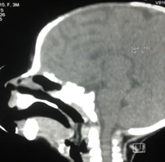

Figure 1 Computed tomography revealed a tumor of 2.5 cm by 0.5 cm pedicled to the left lateral wall of the cavum that fell towards the supraglottis.

Figure 2 No other alterations were found.